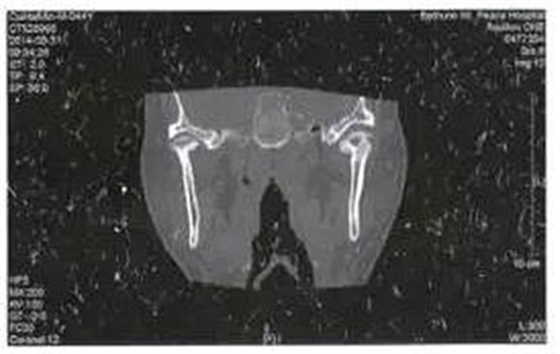

病例4,男,44歲。因左側(cè)耳前反復(fù)腫痛6月就診,檢查左側(cè)耳前區(qū)壓痛,軟組織腫脹不明顯,未見瘺管形成,張口度30mm,張口不偏斜,咬合關(guān)系可??趦?nèi)檢查未見病灶牙,無瘺管形成。全頜曲面斷層片檢查未見埋伏牙齒、囊腫等可能引起感染的病灶。CT掃描顯示左側(cè)髁突關(guān)節(jié)面成蟲蝕樣破壞,中央部分為低密度病變(圖4)。

圖4左側(cè)髁突骨髓炎,關(guān)節(jié)面蟲蝕樣破壞

入院后全麻下采用左側(cè)耳前入路手術(shù),盡量保持升支高度,刮除死骨,放置引流條。術(shù)后18天傷口愈合,疼痛消失。